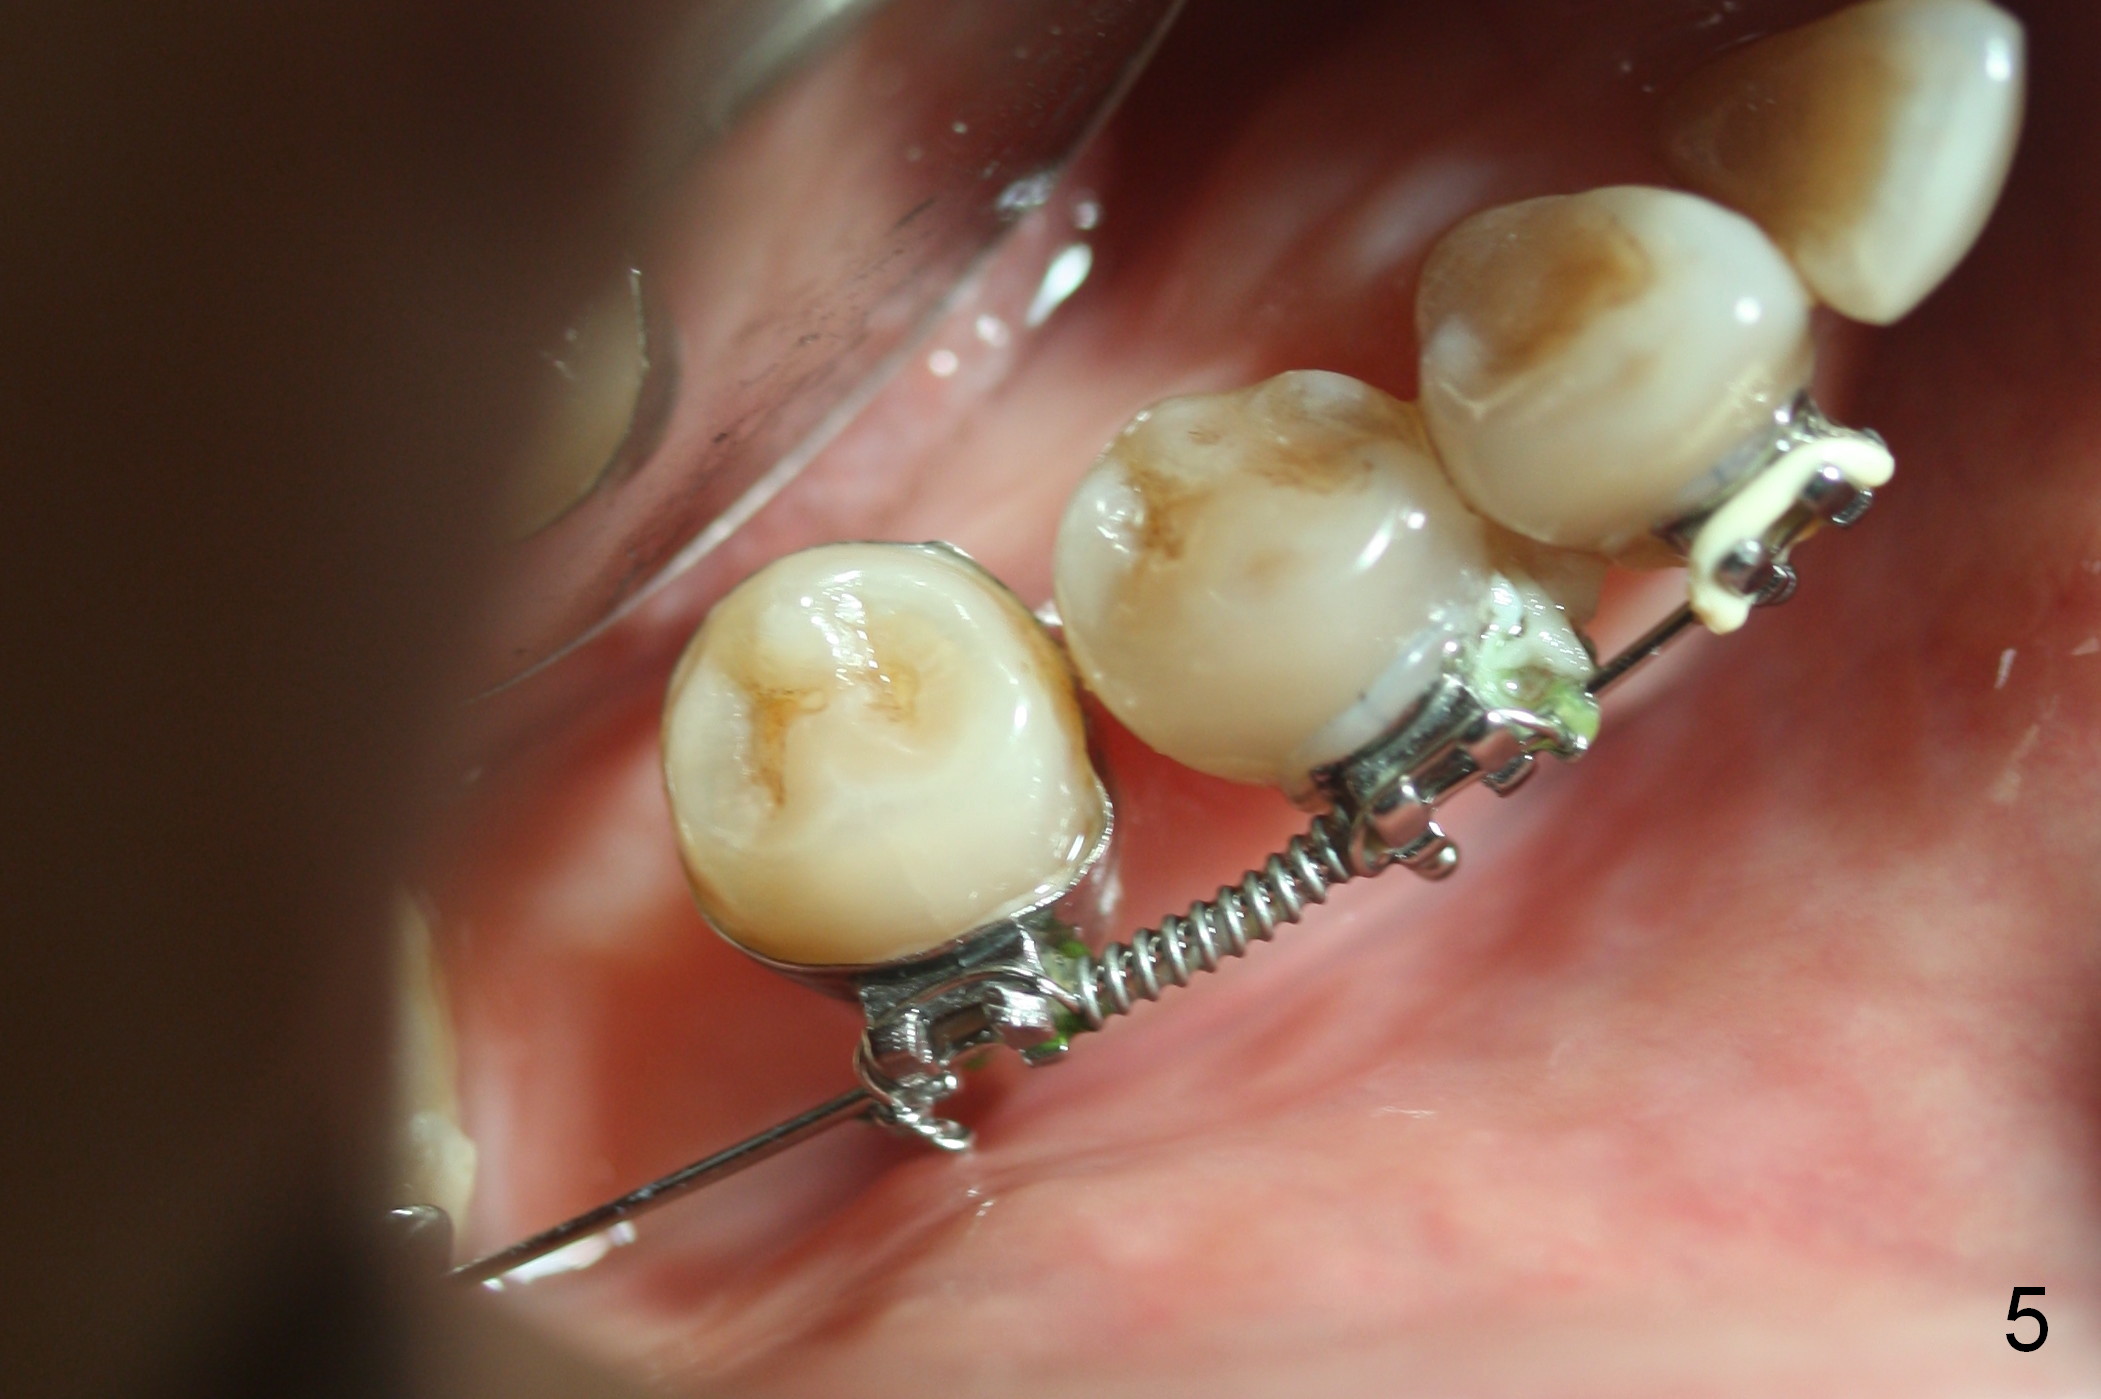

A 47-year-old lady has lost the lower right 1st molar for long time; with reduction of the buccolingual width (Fig.1) and mesiodistal width (Fig.2,3). With regional orthodontic appliance (Fig.4) for 3 months, the tooth #29 has started being distalized (Fig.5). One month and a half later, the tooth #26 starts to shift labially. Power chains and then closed coil spring are placed between #29 and 32. #29 distalization is slow (Fig.7) with closure of the diastema between #31 and 32 (Fig.8, as compared to Fig.1,3). Seven months post banding, a 10 mm miniimplant is placed distobuccal to the tooth #32 (Fig.6); the same 12-mm closed spring is stretched distal by ~ 6 mm (Fig.8 between arrowheads). Two months later, #29 is more distalized (Fig.9 tilted) with bone deposit mesially (*) and coronally (^). A .018' stainless steel wire is installed with an open coil spring placed between #28 and 29 (Fig.10 (^),11). Note #29 rotation (Fig.11). To solve the tilting, a power hook (Fig.12 black) will be clamped to a .016x.016 wire (red), while the closed spring is lowered and attached to the power hook (Fig.12 white). Take photos after removing the existing wire occlusally to show the alveolar width change. When the wire is placed, make sure that the distal wings of #29 bracket is fully engaged to reduce the tooth rotation. Make occlusal adjustment on #31 and 32 to reduce anterior open bite.